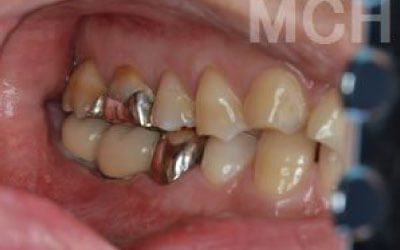

ブリッジ治療では、失われた歯の役割を両隣の歯が補うことになるため、その支えの歯には通常の1.5〜2倍ほどの力がかかるとされています。

入れ歯を使用すると、留め具のバネがかかっている歯や、残っている歯に大きな負担がかかります。多くの方は無意識に残った歯で噛むことが多いため、その歯に過剰な力がかかり、折れたりして寿命が短くなることがあります。

ブリッジ治療では、欠損部分の両側にある歯を大きく削らなければならず、場合によっては虫歯がなくても歯の神経を抜くことがあります。神経を抜いた歯に被せ物をすると、その歯は急速に弱くなり、寿命が短くなるリスクが高まります。

残っている歯にとって、ブリッジ治療は非常にリスクが高い方法です。

その理由は、ブリッジを作るために隣接する歯を大きく削らなければならないからです。

場合によっては、その歯の神経を取ることもあります。それだけ歯に負担をかけるため、歯の寿命が急激に縮んでしまいます。

ブリッジの場合、抜けた歯の前後にある歯を、重度の虫歯と同じくらいまで削る必要があります。

また、抜けた歯の代わりに前後の歯が力を支えるため、その歯に常に1.5倍の負荷がかかります。

2)歯を大きく削る+支えの歯に1.5倍の力がかかる

3)前後の歯の寿命が著しく減る

ブリッジの支えの歯は、データでは10年以内に68%が抜歯になります。